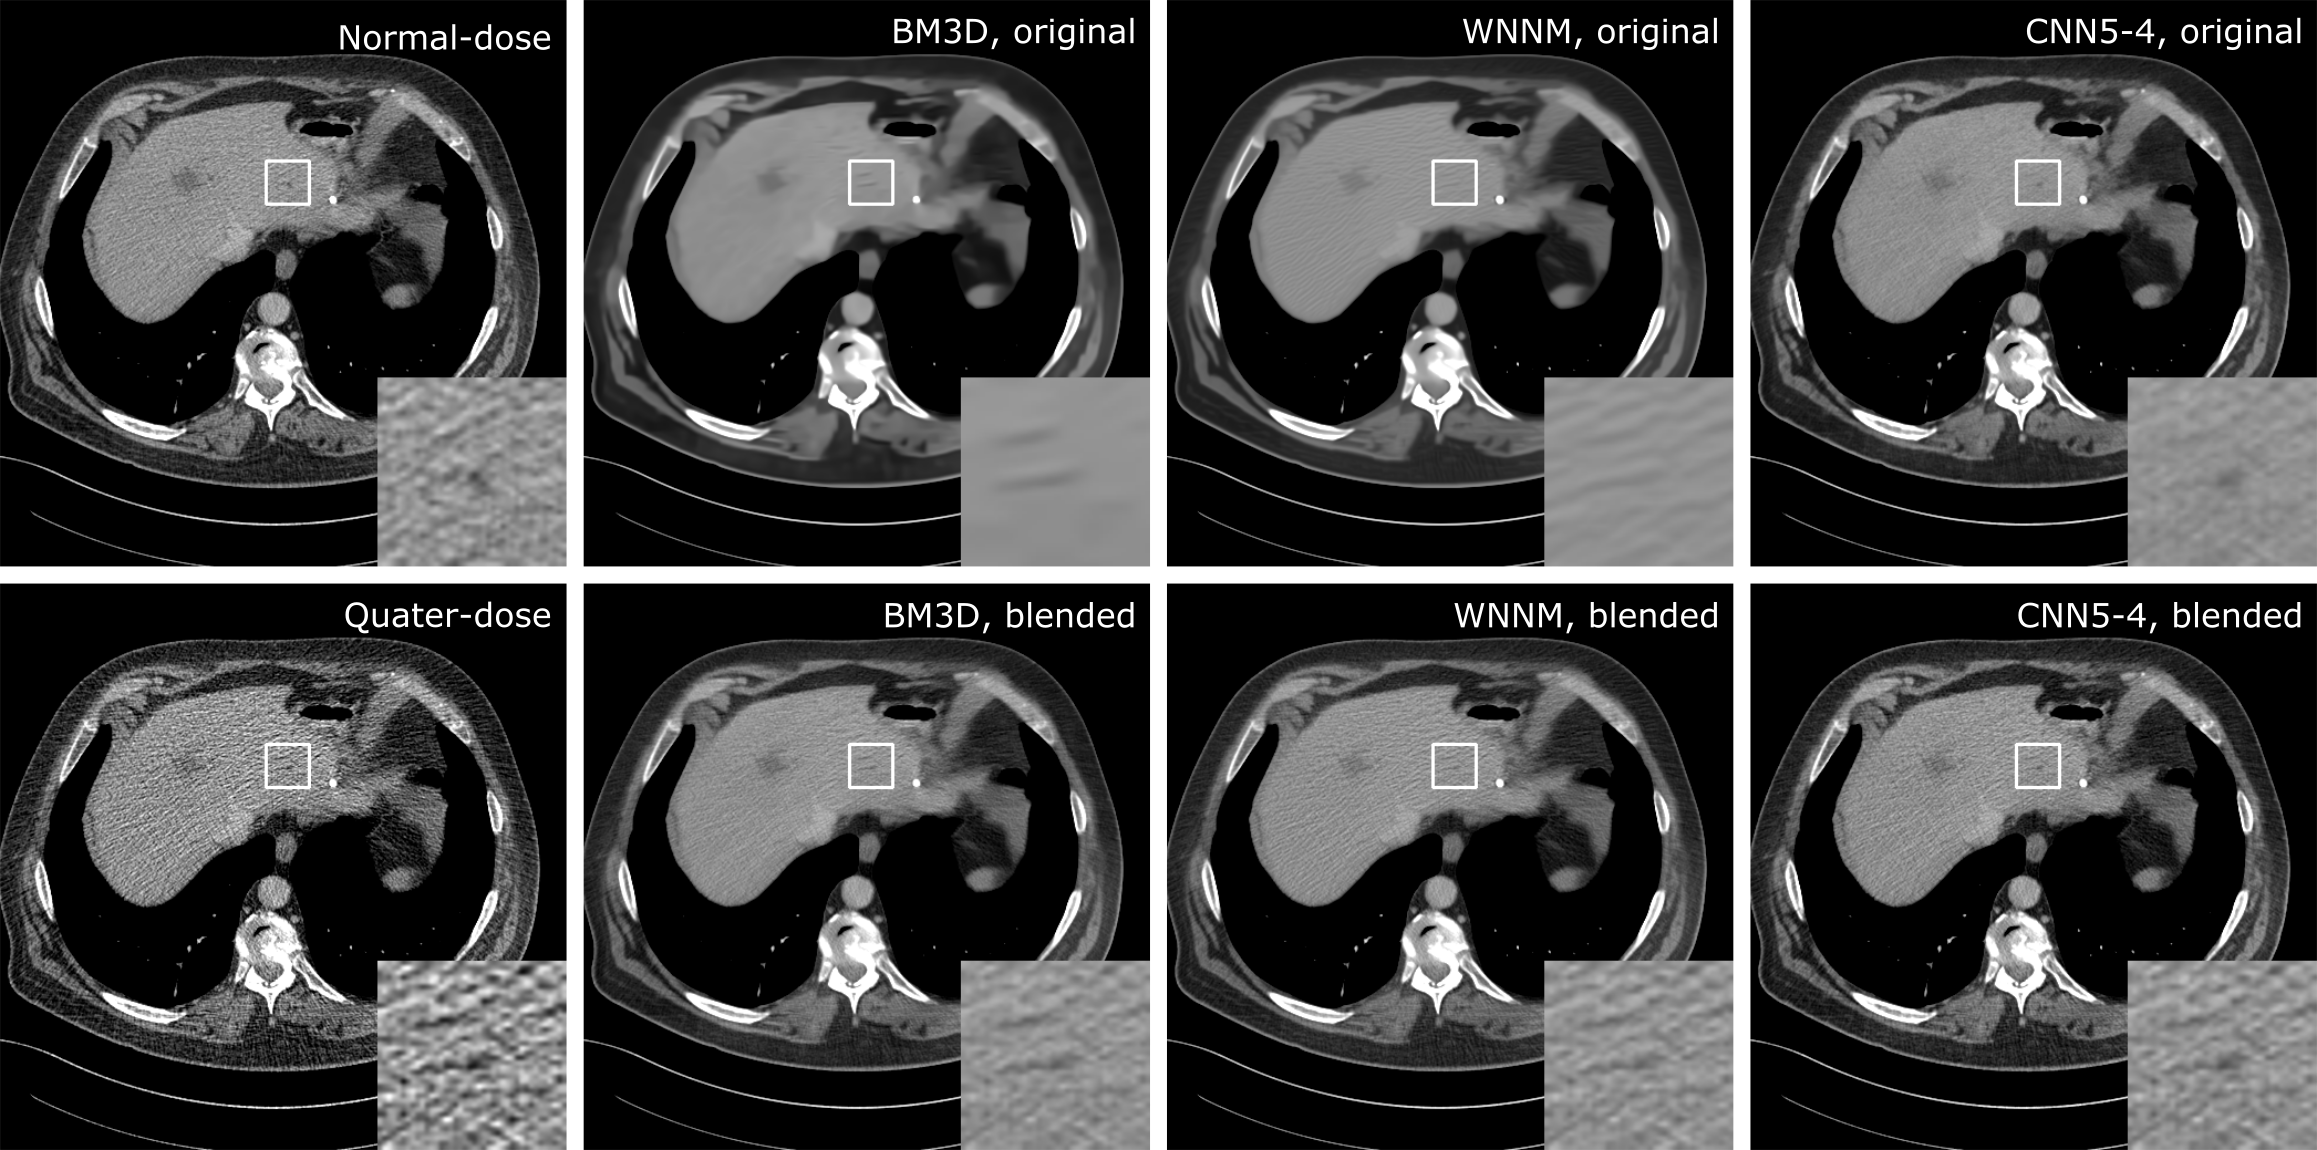

4.3 Comparison with Conventional Denoising Methods

9 slices from the 3 testing datasets that contained lesions were used to compare cascaded CNNs with BM3D and WNNM, and the averaged SSIM compared to the corresponding normal-dose images are listed in Table 1. The neural network based denoisers outperformed BM3D and WNNM for the original denoised images. After blending, BM3D and WNNM had a great gain on SSIM because the low-dose images provided details to the smooth original images. The SSIM of WNNM was higher than that of CNN5-4 and MLP-4 because it had less artifacts. The best performance were achieved by CNN15-3, which were shown in bold in Table 1.

Figure 9 presented the denoising results of a benign cyst in the liver. In the original denoised results, BM3D and WNNM totally missed the lesion and only left the dark streaks near it. On the contrary, cascaded CNN was able to preserve the lesion and remove the surrounding streaks. Thus, in the final blended results, the CNN denoiser could give a more confident confirmation on the lesion than BM3D and WNNM.